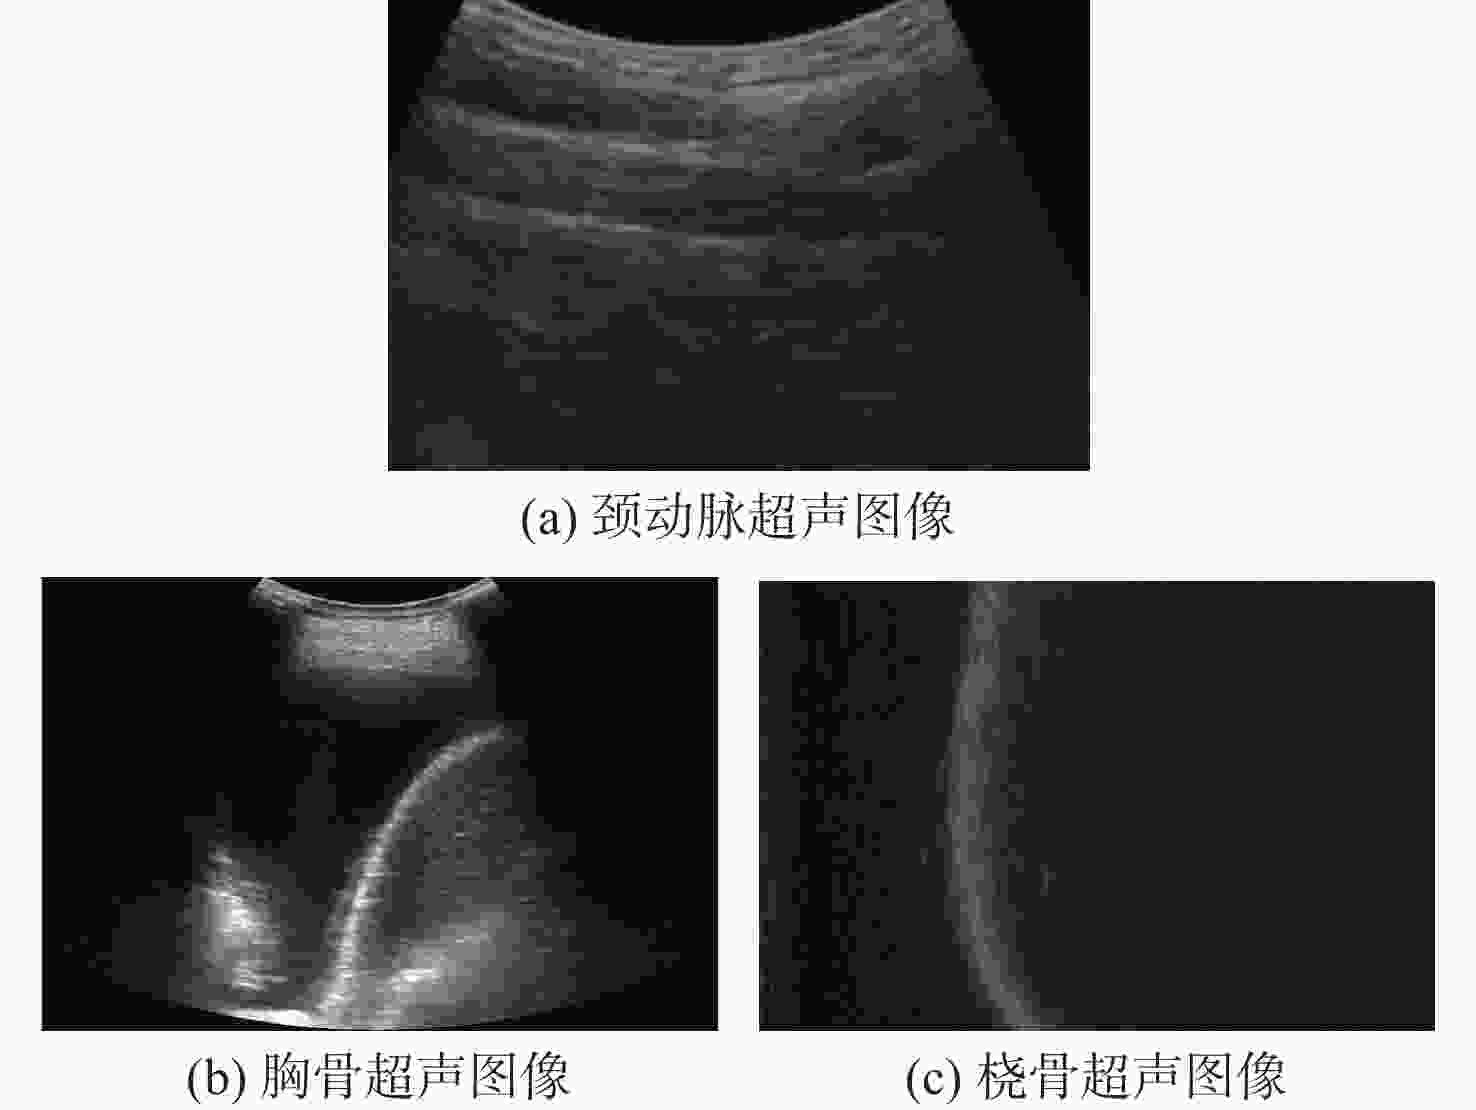

超声成像凭借其经济便携、无辐射、可实时成像等优点,已经成为临床诊断中常用的检查方法之一。血管超声成像不仅可以减少术中射线,也可以实现手术室外血管病变情况的初步判断,满足无法进行造影手术病人的检测需求。超声图像中目标组织边缘特征一般较为明显,综合考虑超声成像的特点及特征分布,选择基于相位对称性的分割算法对降噪滤波后超声图像中的目标组织进行分割,并根据目标组织边缘特性对分割结果进行形态学处理。通过与传统的活动轮廓型及深度学习算法对目标组织边缘的分割效果进行对比及量化分析,验证基于相位对称性的分割算法在目标组织分割及边缘提取中的优势。

Abstract:Ultrasound imaging has become one of the common examination methods in clinical diagnosis due to its advantages of economical, portable, radiation-free, and real-time imaging. Vascular ultrasound imaging can not only reduce intraoperative radiation but also realize the preliminary judgment of vascular lesions outside the operating room, meeting the detection needs of patients unable to undergo digital subtraction angiography. Edges of target tissues in the ultrasonic image are relatively obvious. Comprehensively considering ultrasonic image characteristics and feature distribution, this paper selects a phase symmetry segmentation algorithm to segment the target tissue edges of ultrasound images after noise filtering. Morphological processing is used to optimize the edges of segmentation results. The advantages of the phase symmetry algorithm proposed in this paper are verified by comparing the segmentation results with traditional active contour algorithm and a deep learning model.